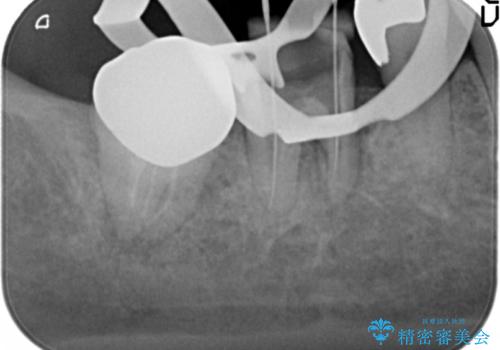

歯ぐきの腫れが治らない 石灰化した狭小根管治療

- 他院で根管治療を受け銀歯をかぶせるところまで行ったが、直後より腫れ・痛みが引かず当院へ相談、来院されました。

X線写真検査より根管充填の行われていない根管、視診より歯肉からの排膿路を認め、急性根尖性歯周炎の治療として根管再治療を計画します。

治療途中、マイクロスコープでも根管が追えないほど狭く細くなった根管へと変性しており根管の拡大形成が難しい状況でした。

CTを撮影し少しづつ丁寧に根管を探索することで無事根管再治療を行い、症状がなくなりました。